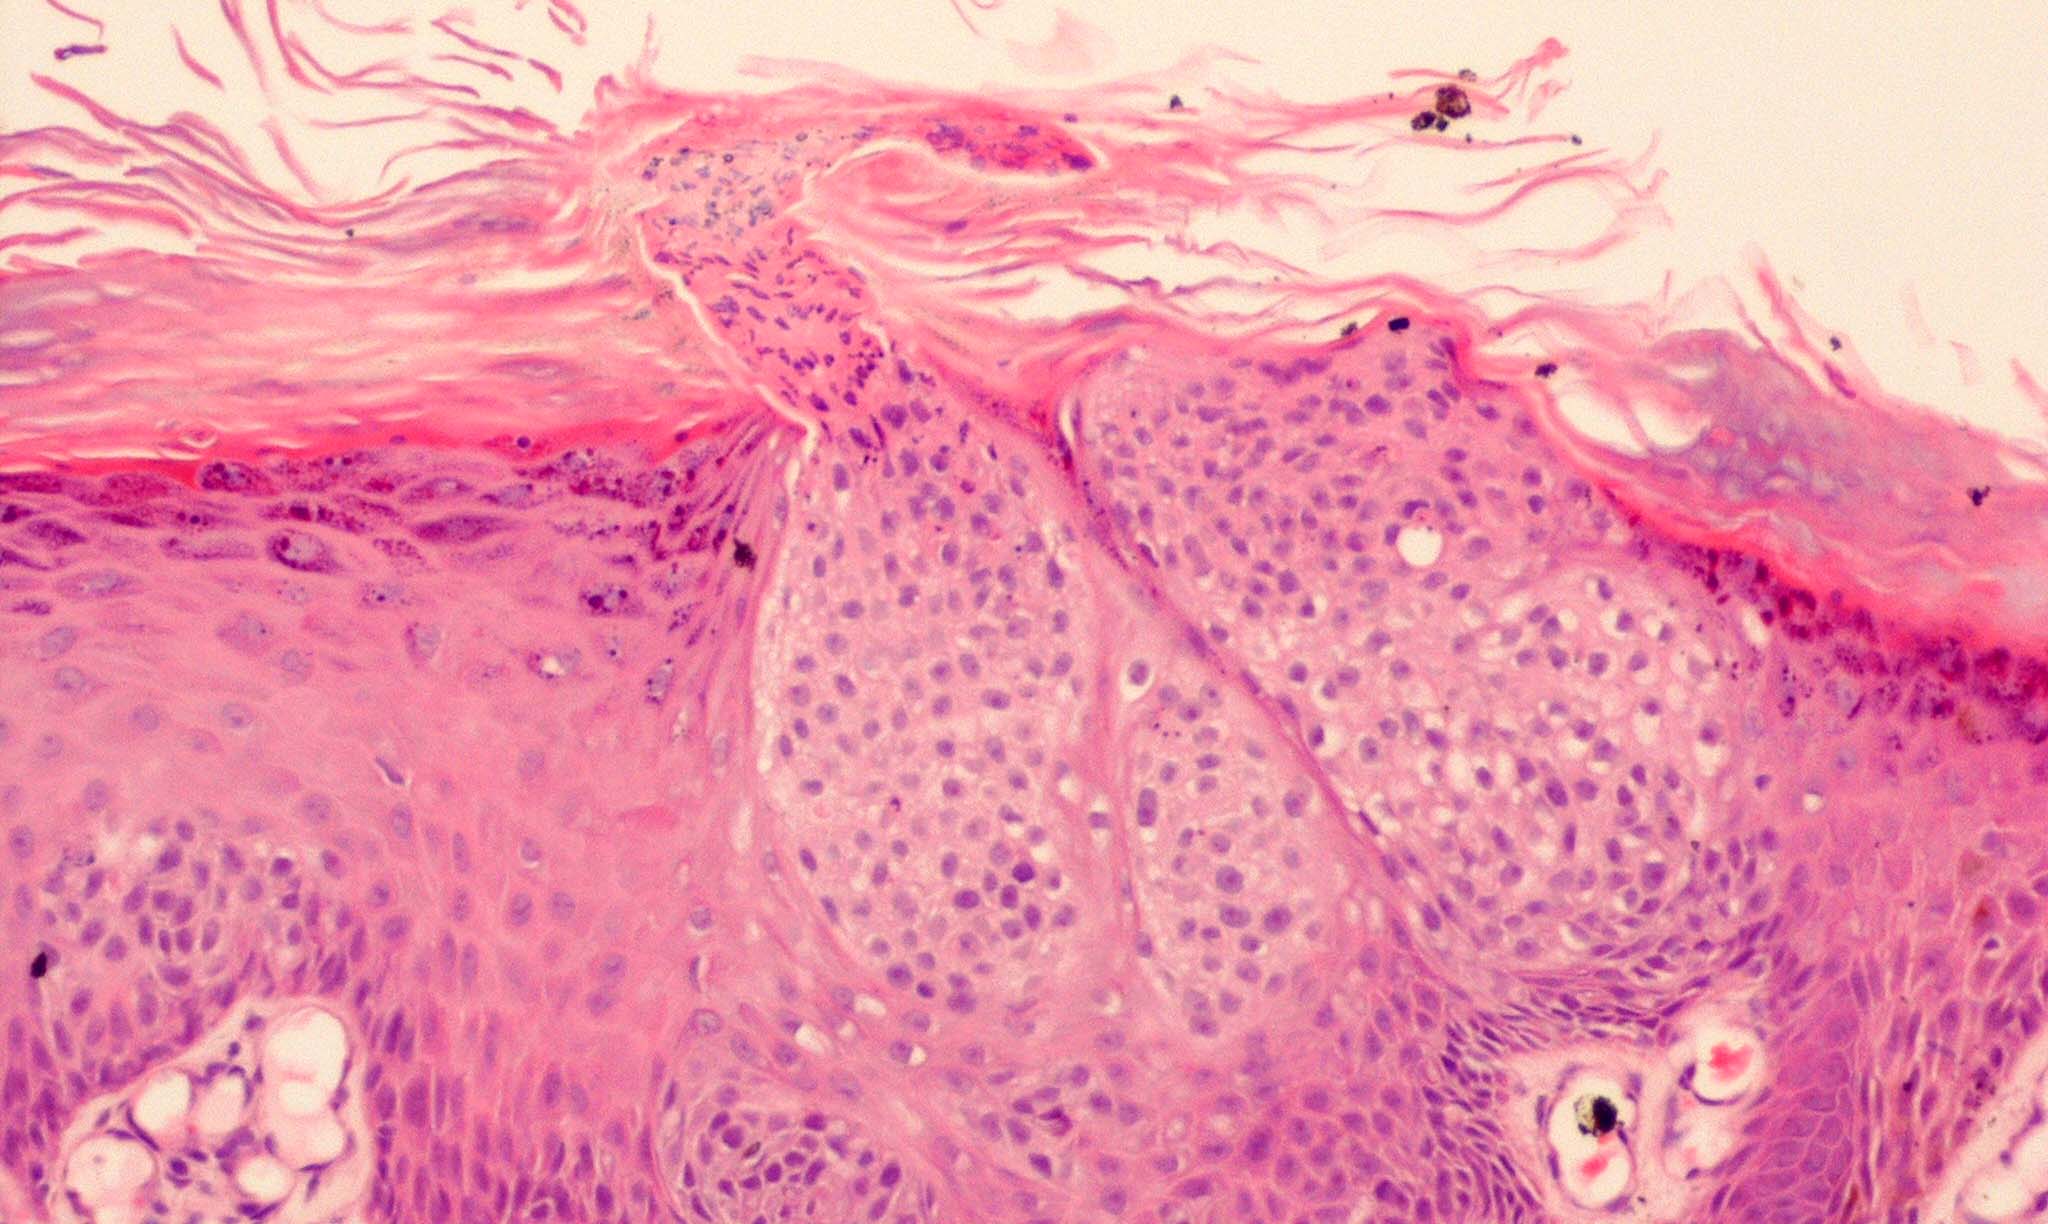

Intraepidermal eccrine carcinoma = الكارسينوما الناتحة داخل البشرة

OLYMPUS DIGITAL CAMERA